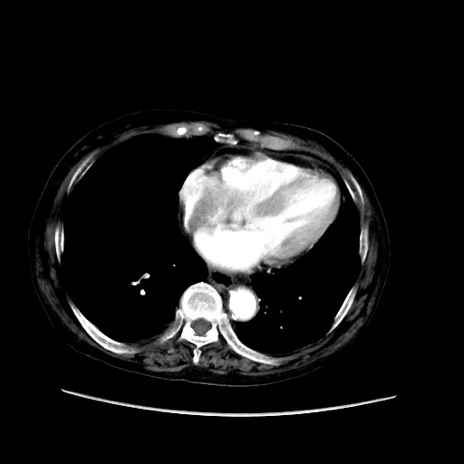

冠状断像

矢状断像

【症例】80歳代 女性

【主訴】腹部膨満感

【現病歴】他院にて肝硬変にてフォロー中。1週間前から便秘、腹部膨満感、臍部腫瘤あり受診となる。

【既往歴】肝硬変

【身体所見】腹部膨隆あり、皮膚変化なし、疼痛なし。

【データ】WBC 4600、CRP 0.25